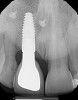

(6.) Pretreatment periapical radiograph.

Figure 6

A 56-year-old female patient was referred for the evaluation of tooth No. 8 (Figure 4 and Figure 5). A periapical radiograph indicated that the tooth had undergone apicoectomy and received an excessively long post (Figure 6), and a cone-beam computed tomography (CBCT) scan of the site revealed a lack of buccal plate bone (Figure 7).